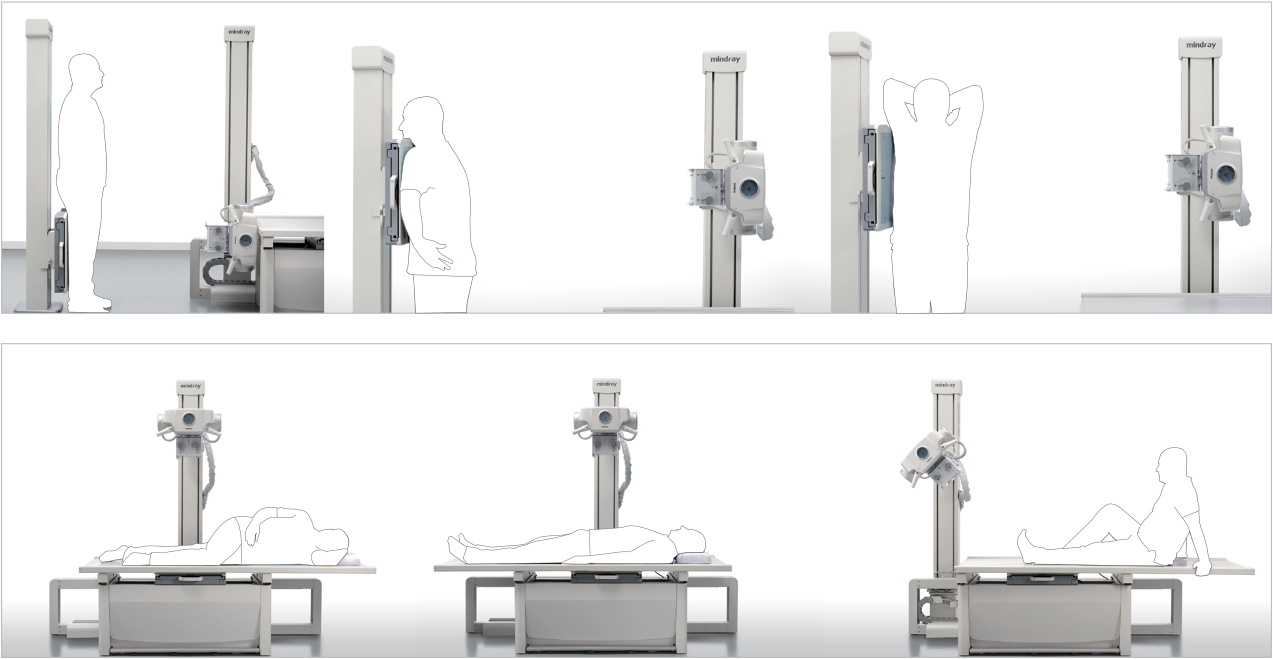

Posicionamiento flexible y eficiente:

El posicionamiento es el mismo que con la radiograf√≠a convencional y no se produce ning√Їn cambio al respecto.

Es posible cambiar con rapidez de una posición horizontal a una vertical. Además, la mesa flotante fija permite reducir en gran medida el tiempo necesario para mover a los pacientes y mejorar el rendimiento.